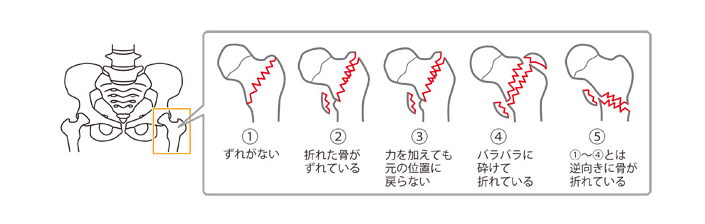

大腿骨頚部・転子部骨折の種類

大腿骨頚部骨折

大腿骨頚部骨折は、折れた骨の状態から4段階に分類されます。

4つの各段階の状態は、以下のとおりです。

出典:Mindsガイドラインライブラリ 大腿骨頚部/転子部骨折 Minds版やさしい解説

大腿骨頚部骨折の分類の詳細

| 非転移型 | ❶ もっとも軽度な骨折で、完全には折れておらず骨にひびが入っている状態 ❷ 骨は完全に折れてはいるが、折れた骨がずれたりしていない状態 |

|---|---|

| 転移型 | ❸ 折れた骨が少しずれ、折れた部分がぴったりと合わない状態 ❹ 折れた骨が大きくずれ、折れた部分がぴったりと合わない状態 |

出典:Mindsガイドラインライブラリ 大腿骨頚部/転子部骨折 Minds版やさしい解説

大腿骨転子部骨折

大腿骨転子部骨折も、折れた骨の状態によって5段階に分類されます。

5つの各段階の状態は、以下のとおりです。

出典:Mindsガイドラインライブラリ 大腿骨頚部/転子部骨折 Minds版やさしい解説

転子部骨折の分類の詳細

大腿骨頚部骨折は、折れた骨の状態から4段階に分類されます。

4つの各段階の状態は、以下のとおりです。

| 安定型 | ❶ 骨に亀裂が入っているが、回転したりずれたりしていない状態 ❷ 折れた骨がずれているが、力を加えなければ元の位置に戻る状態 |

|---|---|

| 不安定型 | ❸ 折れた骨がずれて、力を加えても元の位置に戻らない状態 ❹ 骨が折れて粉々になってしまった状態 ❺ 骨の折れ方が❶〜❹とは逆の方向になっている状態 |

出典:Mindsガイドラインライブラリ 大腿骨頚部/転子部骨折 Minds版やさしい解説

https://minds.jcqhc.or.jp/n/pub/3/pub0016/G0000622/0008